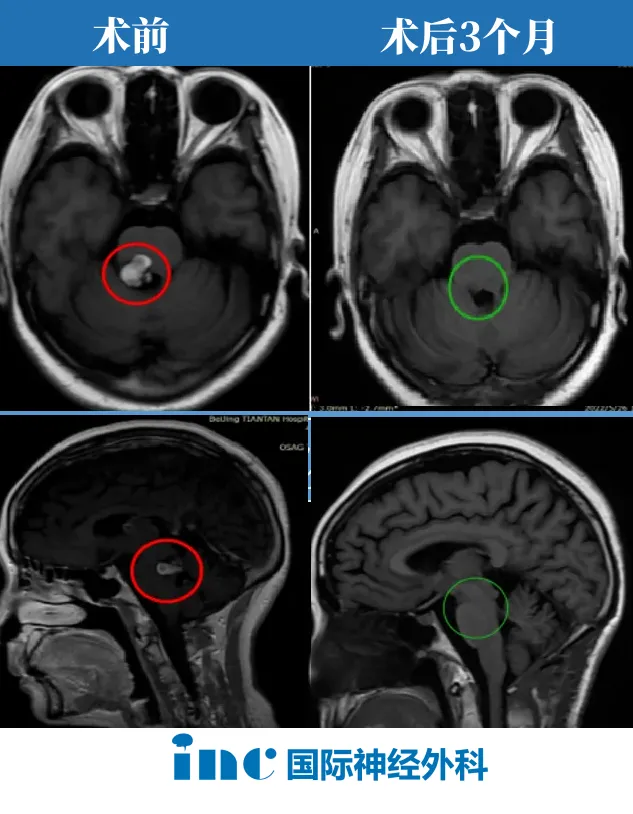

显微手术全切病灶及术后三月随访结果

术中,巴教授凭借对脑干解剖结构的精准掌握及娴熟显微外科技巧,谨慎避开正常神经组织,精确定位病灶——最终实现脑干海绵状血管瘤完全切除。

术后三月复查MRI,影像结果证实好消息:病灶全切,无残留。

虽然右侧下肢功能仍需康复训练,但"病灶再出血"风险已彻底消除,生活质量获得显著改善。